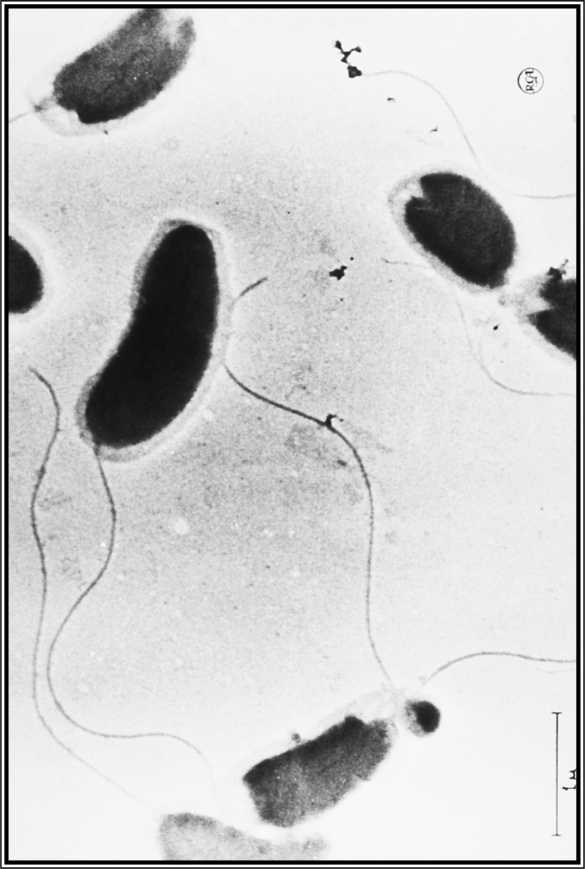

Холерный вибрион под микроскопом